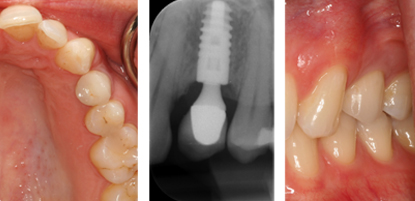

SINGLE DENTAL IMPLANT

Those who have a single tooth missing often choose Dental Implants for replacement as it comes closest to imitating a natural tooth. Implants are also long-lastingly sturdy since they are fused to the jawbone and can stably stand on their own. Dr Bopanna offers uncompromising attention to detail, and uses the latest equipment to craft your new tooth.

Single tooth replacement is normally carried out in three stages. The failing tooth is extracted and an implant is placed into the socket or it can be placed after complete healing has occurred (3 months). After allowing the bone and gum to heal around the implant a scan body is attached to the implant/s and a 3d digital impression is taken. The scan is then uploaded to either Atlantis or Exocad and the abutment is designed, after which the stl file(3D file) is used to design the crown which fits on top of the implant. All of these stages can be carried out in the single appointment depending on need and condition of the patient.

FAILING TOOTH

Card image Actual Practice Photographs ©Dr.Pavan Bopanna

IMPLANT PLACEMENT

Card image Card image Card image Card image Card image Actual Practice Photographs ©Dr.Pavan Bopanna

CROWN FITTED